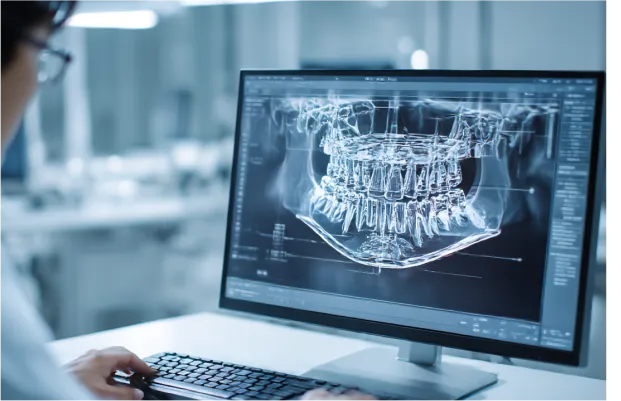

歯科用CTによる3D精密診断

歯科用CTは、レントゲンでは見えづらい顎の骨や神経の位置を、3Dの立体画像で確認できる機器です。

精密なインプラント治療のために、「見える化」するのが歯科用CTの役割です。

コンピューターシミュレーションによる

治療計画CTで撮影した3Dデータを専用ソフトに取り込み、コンピューター上でインプラント手術のシミュレーションを行います。

- インプラントの種類・サイズ

- 埋入の角度・深さ

- 仕上がりのイメージ

これらのシミュレーションを行い、手術時のトラブル対策をします。

歯科用CTは顎の骨や神経・血管の位置を3Dで詳しく撮影できる装置です。普通のレントゲンは平面画像で、骨の厚みや位置を正確に把握しづらいです。